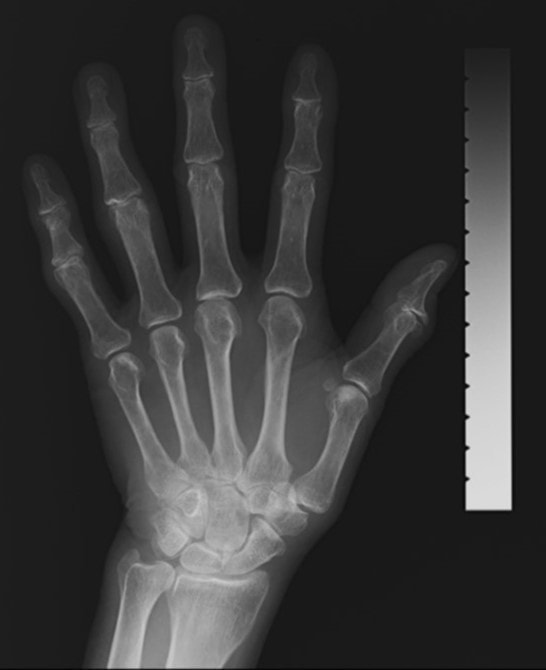

当院では左手を撮影するDIP法を行なっております。極めて少ないX線量で行う低侵襲な検査法です。